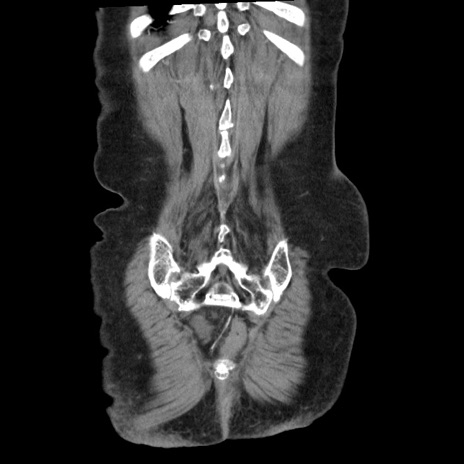

症例1(冠状断像)

矢状断像